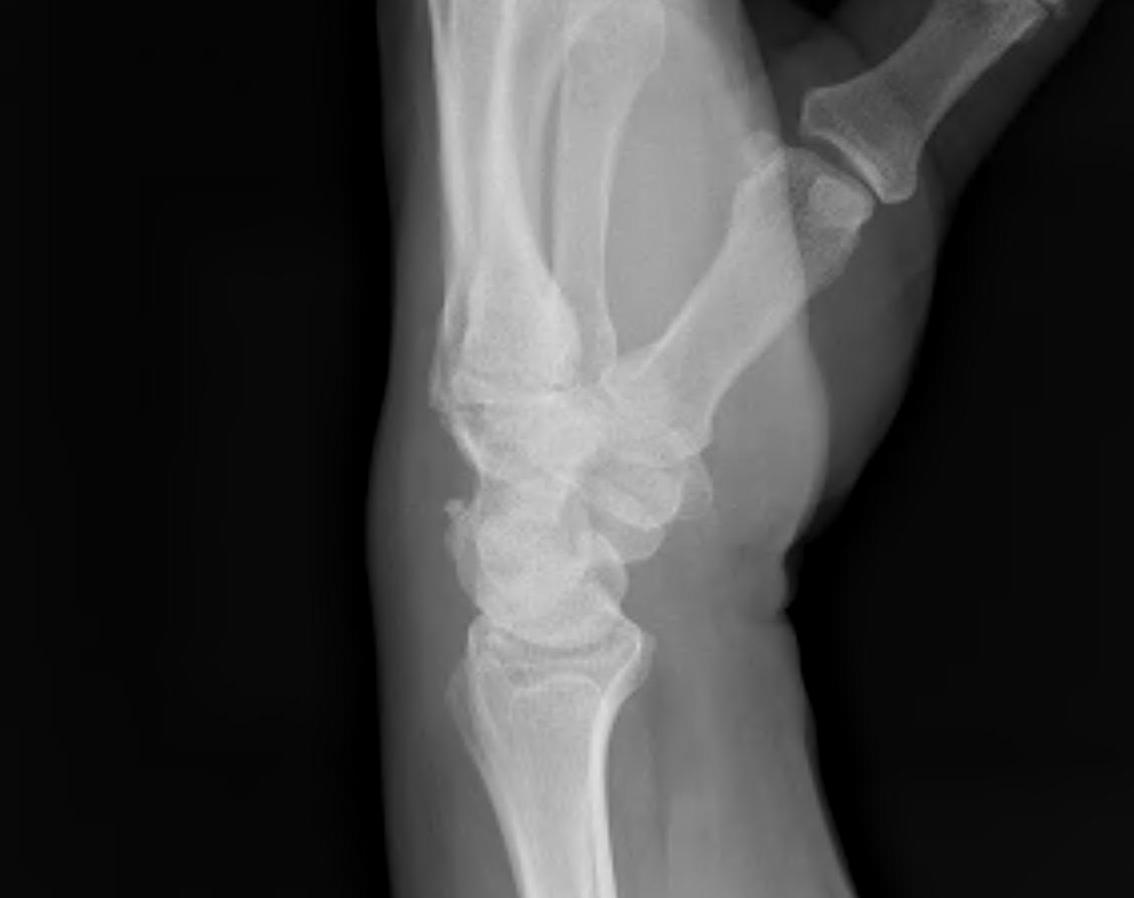

Lateral

Palmarflexion of scaphoid

Dorsiflexion of lunate

Increased scapholunate angle

- > 70o

- usually 30 - 60o

Increased luno-capitate angle

- normally < 10o

Increased radio-lunate angle

- lunate extended > 10o